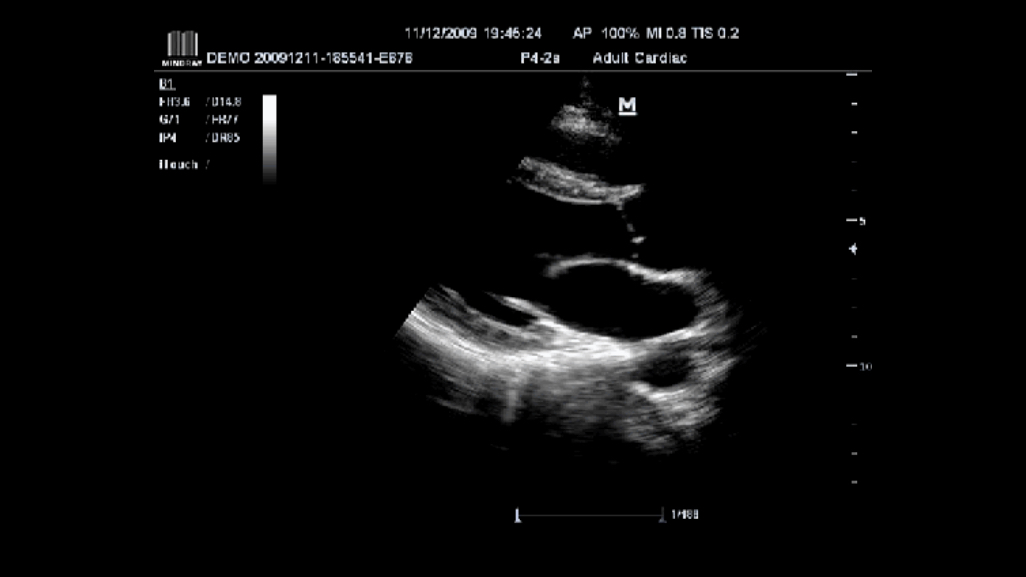

Award winning portable hand-carried color Doppler, M7 premium is a High level system with excellent performance. Equipped with dedicated cardiac package and easy-to-use workflow software, M7 premium offers an ideal packaged solution to address the needs of cardiologists.

Tissue Doppler Imaging with Quantitative Analysis (TDI and TDI-QA)

Supported by MindrayŌĆÖs unique 3T technology with single crystal, the M7 premium significantly improves the performance of Tissue Doppler Imaging. With the added quantitative analysis package with comprehensive parameter outputs such as velocity, strain and strain rate, the TDI-QA performs with ease at the bedside.